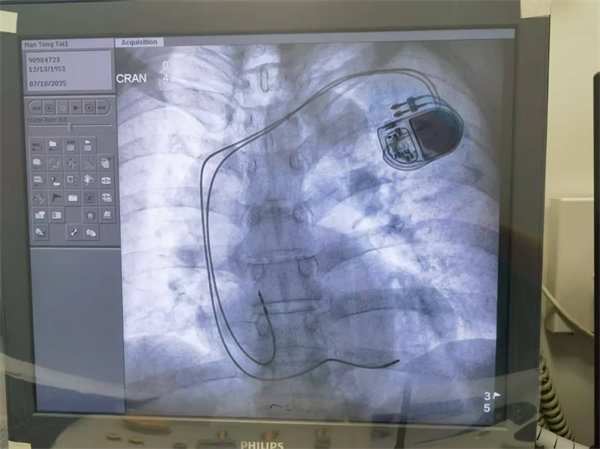

心血管內一科團隊迅速完善心電圖、心臟超聲、動態心電圖等檢查,結合患者病史制定精準診療方案。考慮到藥物治療難以根治,且患者心律失常類型復雜,同時團隊根據患者病情及個人意愿,選擇了進口雙腔永久抗核磁起搏器,于是團隊決定為其實施雙腔永久起搏器植入術。

7月10日,在白志生的主刀下,手術順利完成,成功為患者植入起搏器以維持正常心率。術后經過抗動脈硬化、抗心律失常等藥物治療及精心護理,患者心率穩定在60-85次/分,各項指標逐步恢復正常,8天后便康復出院。

術后患者恢復良好